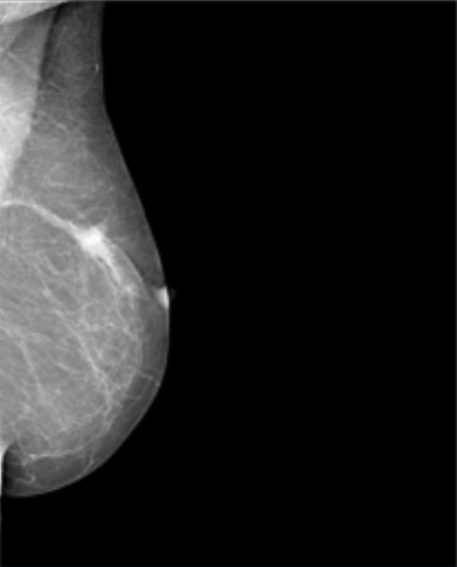

Datos Clínicos: Paciente Femenino de 48 años.

Diagnóstico: Calcificación Negativa.

Dimensiones: 632 x 548.